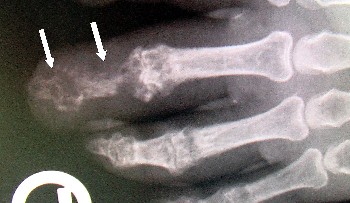

Остеомиелит Пальца Фото

Остеомиелит Пальца Фото 138 фотографий